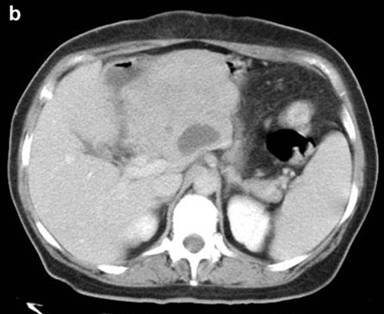

Given these clinical findings and complementary tests, an exploratory laparotomy was performed. A large, well defined, encapsulated, retroperitoneal and mesenteric mass was found involving the head and the body of the pancreas, portal and superior mesenteric vessels encasing the mesenteric root from Treitz’s angle and spreading into the mesenteric fat. On partial excision, the mass was tough and white fibrotic-like (Figure 2). Intra-operatory microscopic study suggested malignant fibrous histiocytoma. Tumor involvement of the main mesenteric vessels and the whole mesentery did not allow curative resection.

Figure 2. Macro-biopsy (4.5 cm in diameter) obtained from the exploratory laparotomy showing tissue with a yellowish, nodular and polished surface. |